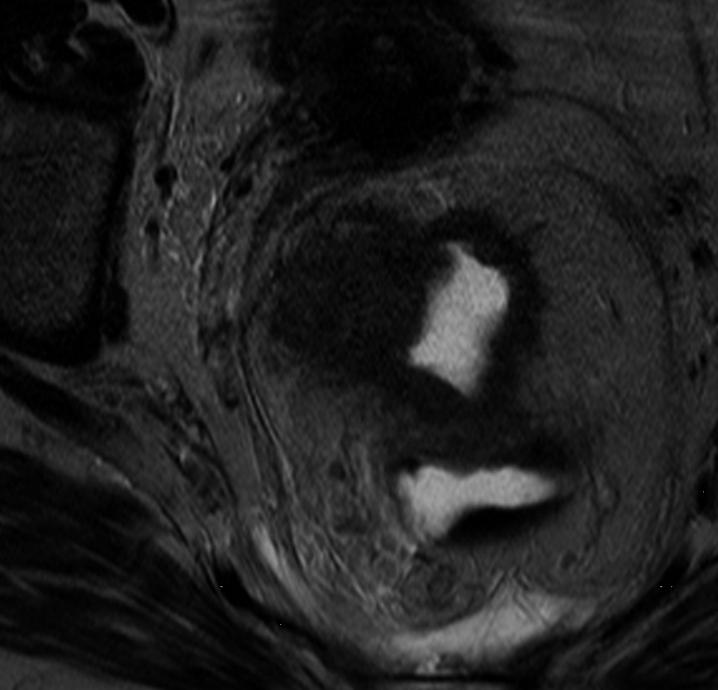

IRM rectale en T2, coupe axiale.

Publié par : Kamal nadifi